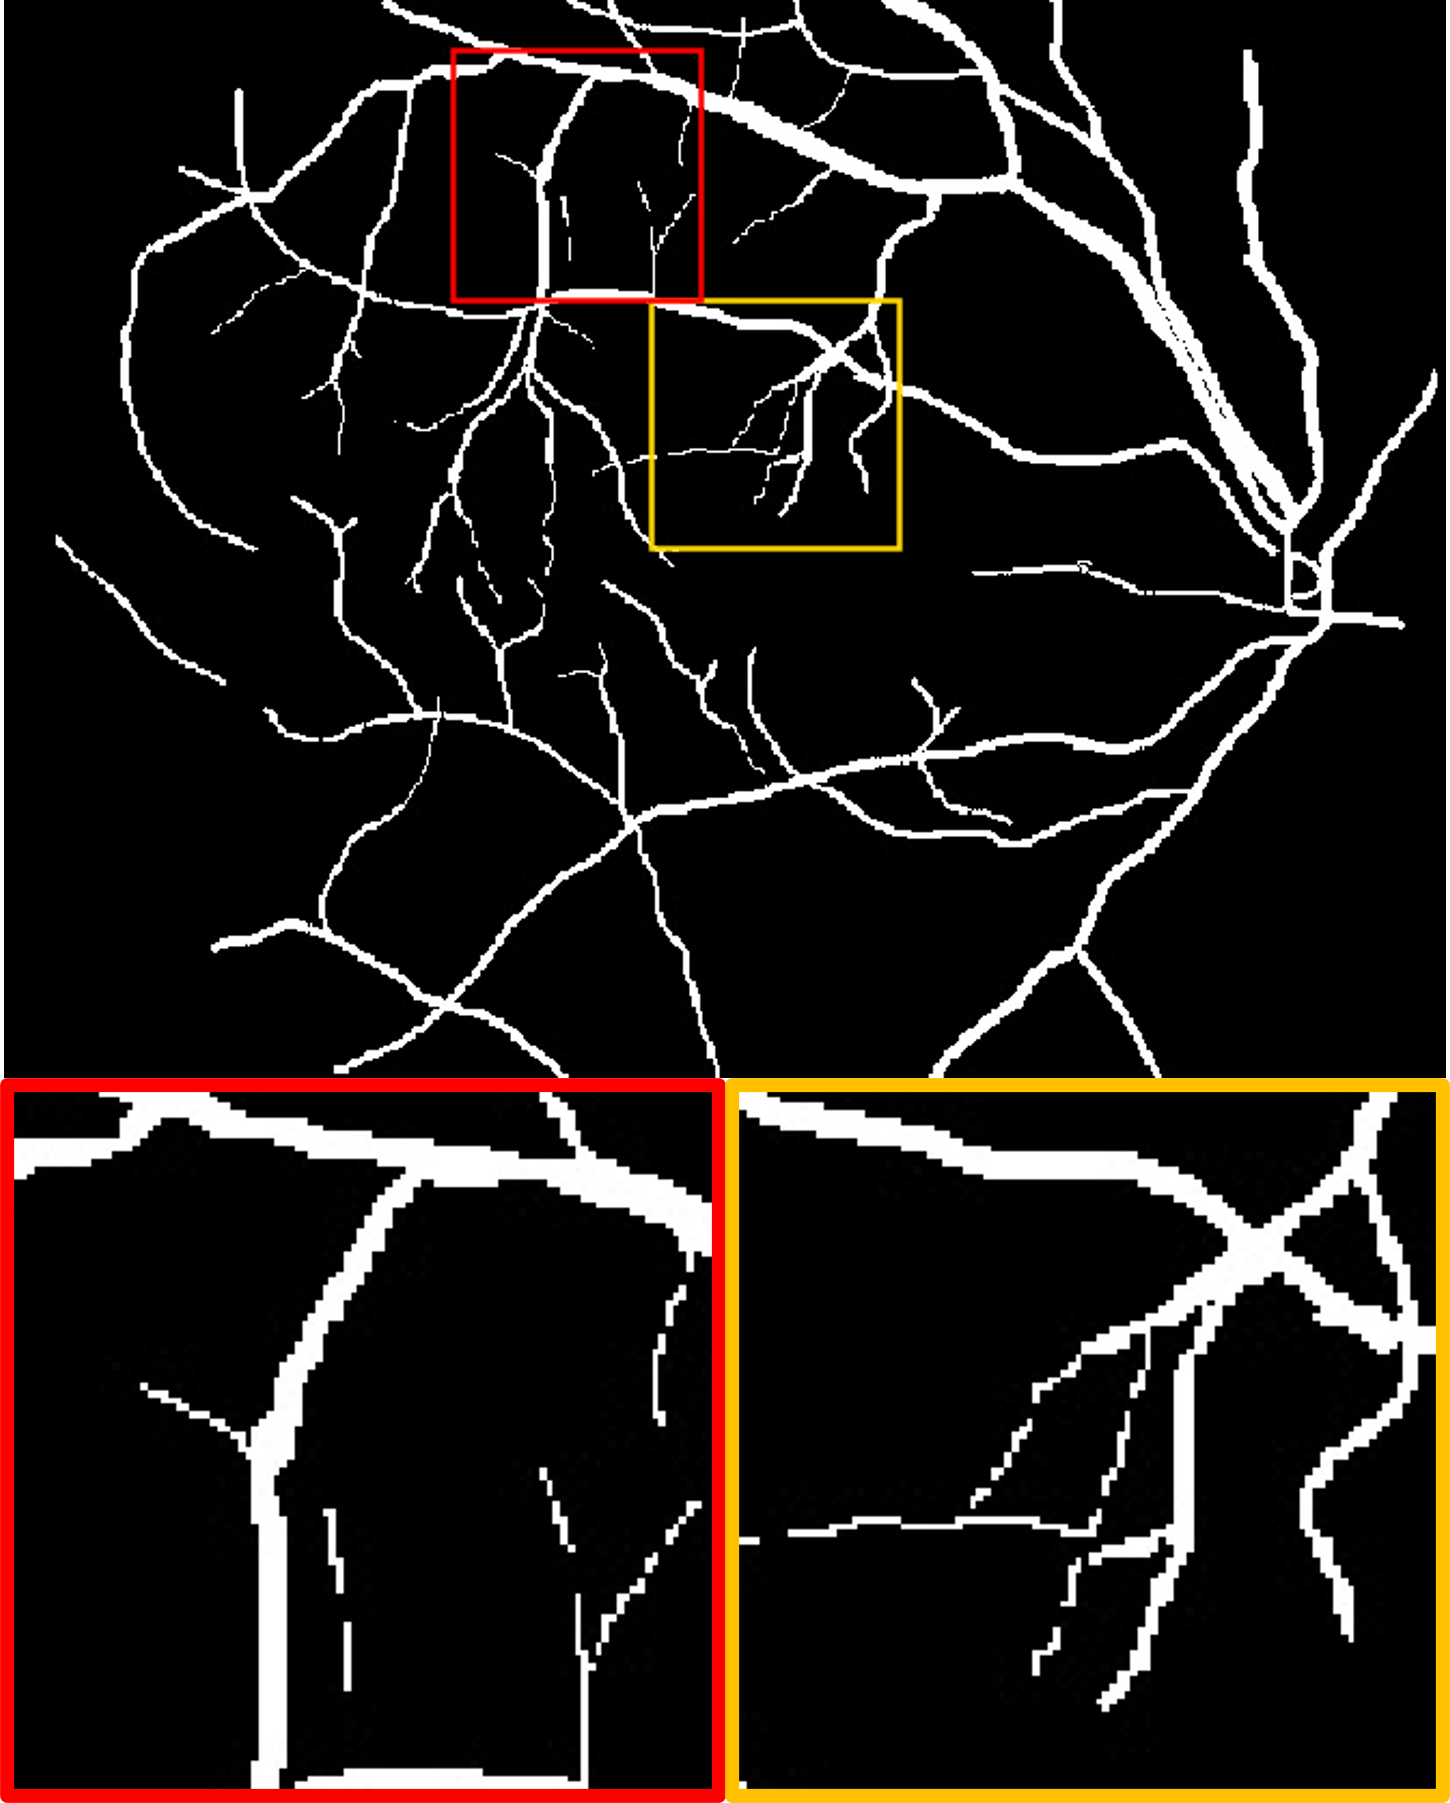

Datasets. We use four publicly available fundus datasets as shown in Fig. 1(b). The DRIVE dataset [15] consists of 20 labelled images of size . The HRF dataset [16] contains 45 labelled images of size . The STARE dataset [17] includes 20 labelled images of size . The ARIA dataset [18] includes 138 labelled images of size . DRIVE and HRF are set as source domain, whereas STARE and ARIA are used for testing.

Fig. 2 shows a test example from each of the target domains. We observe that for different datasets, the manual annotations includes varying amounts of detail: the label for the STARE dataset contains many more small vessels than ARIA. In the ARIA example, the deep angiogram is able to enhance the thin vessels with very poor contrast. This is also evident by the big vessels seen at the bottom left quadrant of the image where the illumination is low. Moreover, the angiogram filters out the circular artifacts seen within the red box. In the STARE example, our model extracts most of the vasculature including the faintly visible fine vessels. These tiny vessels have relatively lower intensity in the deep angiogram, which suggests lower confidence. Compared to the manual label, the deep angiogram can also delineate the vessel diameter more precisely.